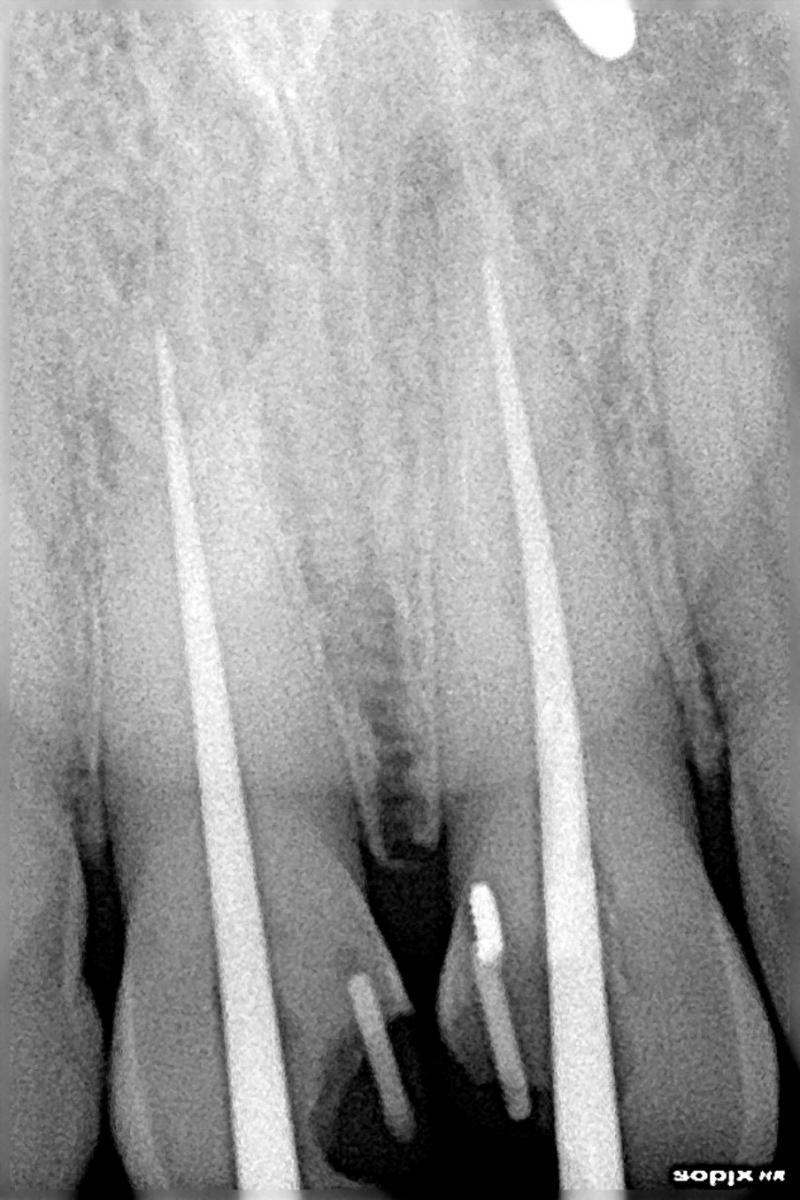

RE-TREATMENT ROOT CANAL CASE OF ANTERIOR

TEETH (FRONT TEETH)

ROOT CANAL DONE BY GERMAN DENTIST FAILED (IMPROPER ROOT CANAL OBTURATION)

Re treatment of the same done at cheema dental

Before After